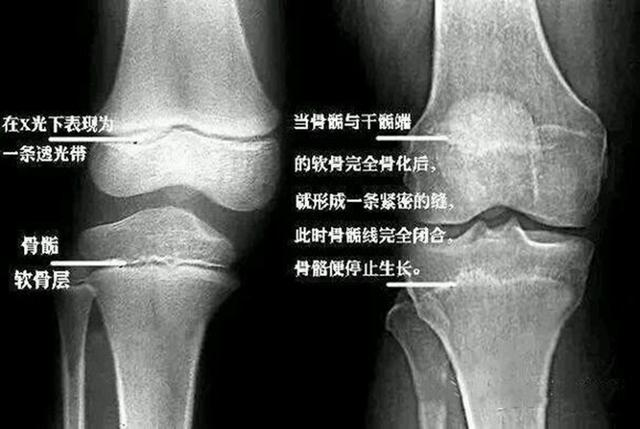

殊不知 , 孩子性早熟并不只是“成长提前了”这么简单 , 还会带来一系列危害 。 比如提前发育的外观 , 会让孩子觉得自己跟同龄人不一样 , 从而有自卑、羞耻感等心理 。 另外 , 性早熟还会让骨龄提前 , 引起骨骺线提前闭合 , 导致孩子达不到遗传身高 。